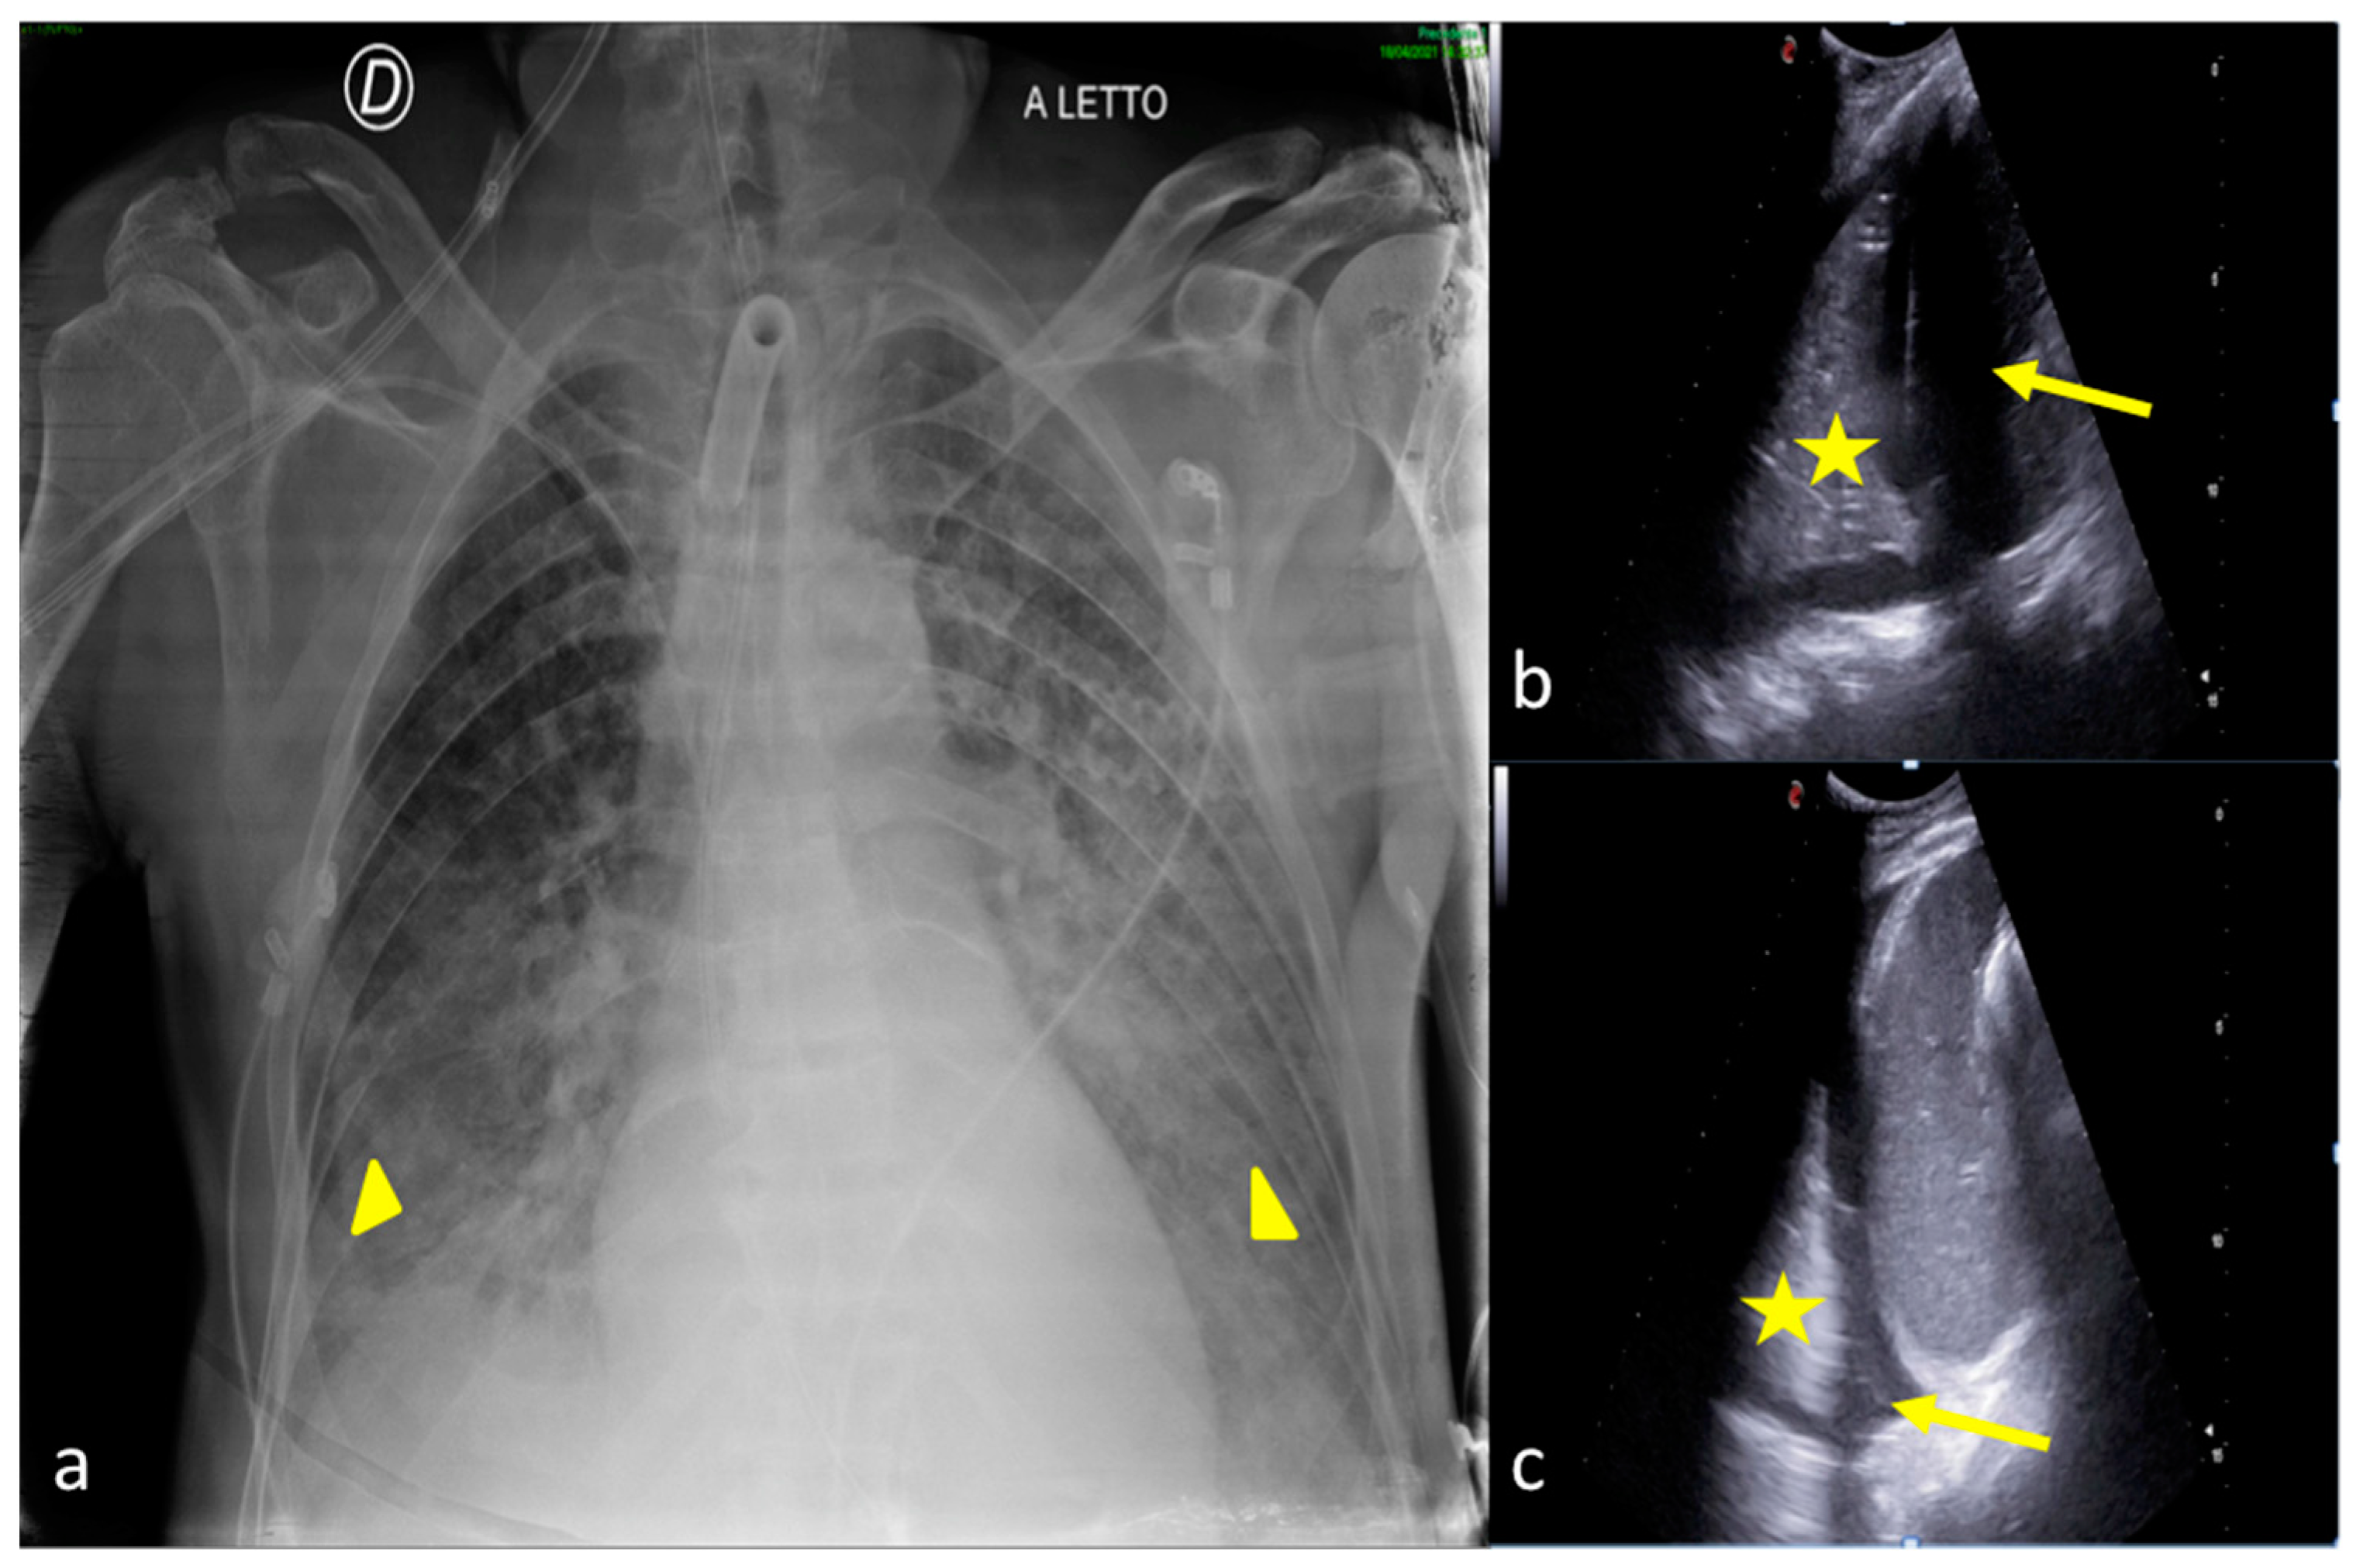

2.1. Atelectasis

2.3. Pleural Effusion